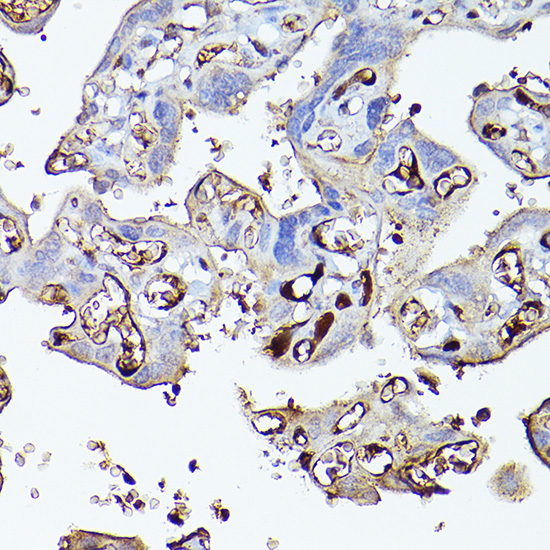

Immunohistochemistry of paraffin-embedded human liver cancer using Complement factor H Rabbit pAb.

,

Immunohistochemistry of paraffin-embedded human placenta using Complement factor H Rabbit pAb.